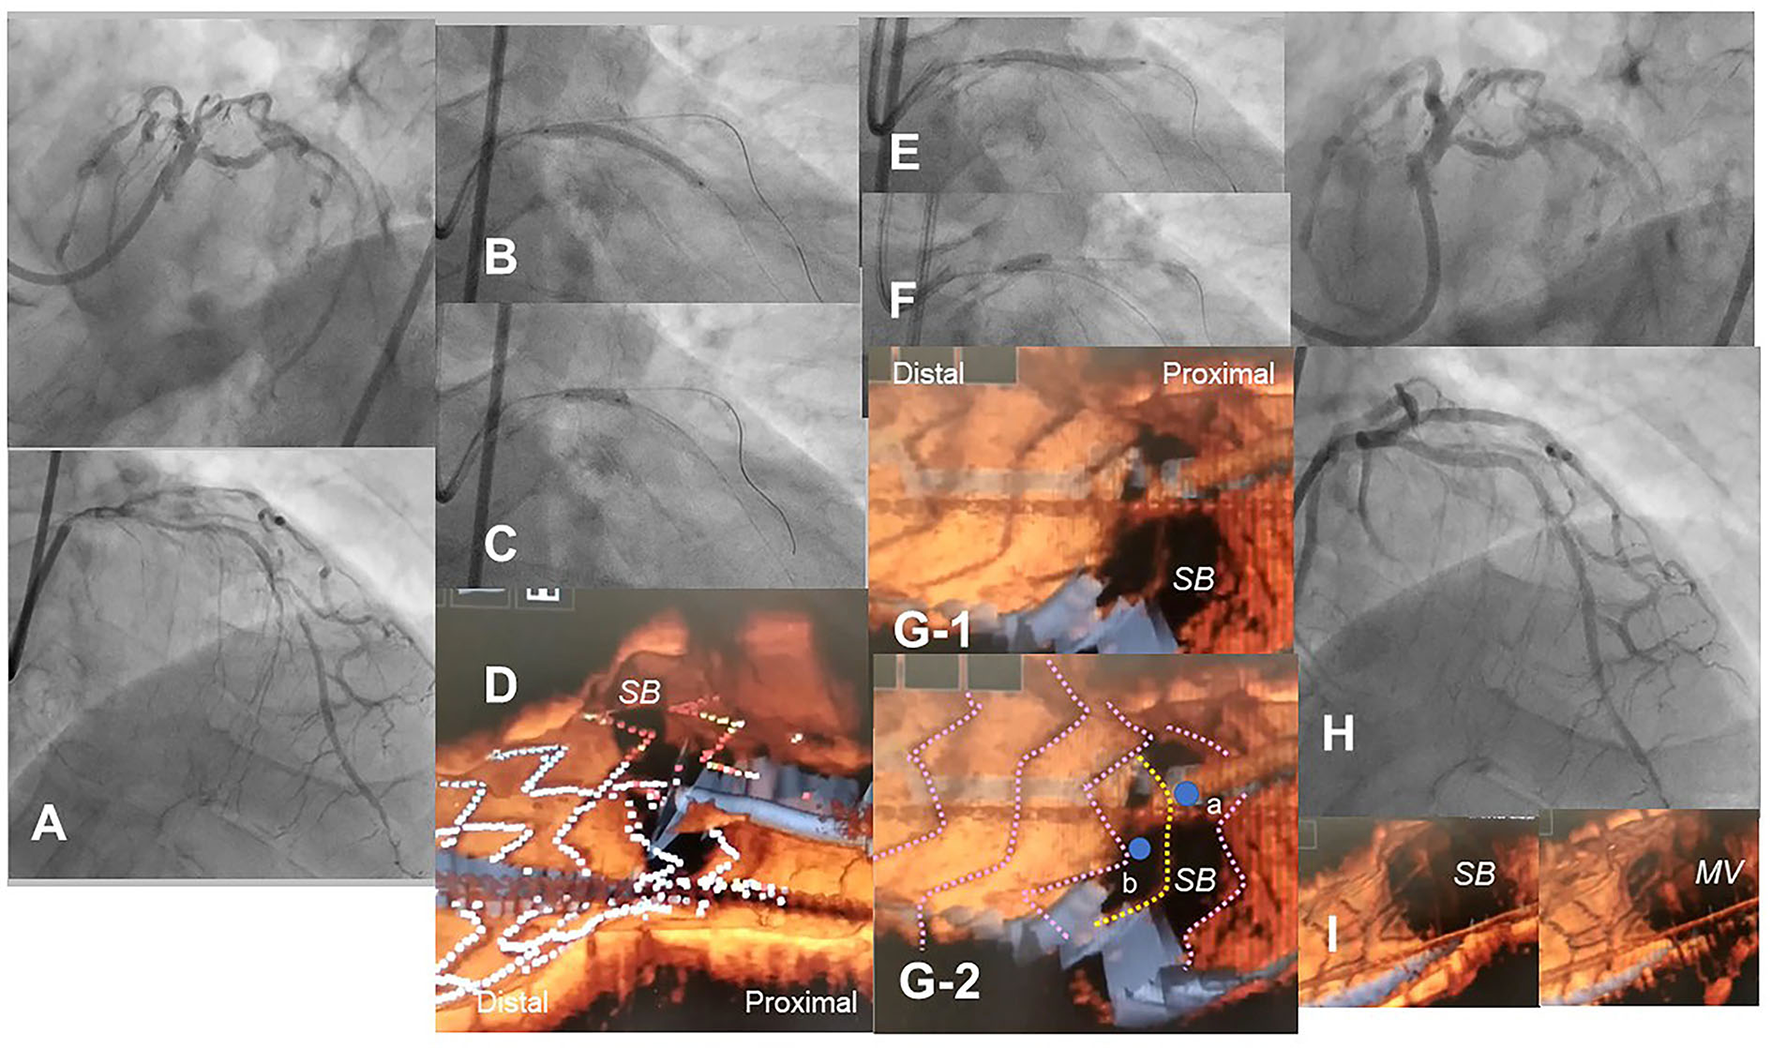

Figure 8

Optical coherence tomography (OCT)-guided culotte stenting after rotational atherectomy in the calcified bifurcation lesion. A 72-year-old man with Medina 0-1-1 calcified lesion in left anterior descending artery (LAD)-diagonal bifurcation (A) was treated with culotte stenting after rotational atherectomy in both branches (Supplementary Movie 11). Rotational atherectomy using 1.75 mm and 2.15 mm burrs was performed in both LAD and diagonal branch, and OCT shows adequate ablation. A Ultimaster 3.0/33 mm stent was implanted from proximal LAD to diagonal branch (B) followed by proximal optimization with a 3.75 mm balloon (C). 3D OCT showed the guidewire recrossed in the distal cell which occupied most largely in the diagonal branch ostium in the Link-free type that some proximal hoops of the far-distal cells with link-connection remained at the carina (D). After the dilation of diagonal branch ostium, an Ultimaster 3.0/33 mm stent was deployed in the LAD (E) followed by proximal optimization with a 3.75 mm balloon (F). The guidewire seemed to recross in the middle part of the jailing cells (G-2, point a), and more distal part (G-1, point b) seemed to be optimal. However, the strut alignment of the MV stent was indicated as pink lines and the most distal strut indicated by yellow lines was turned out to be the remained hoop of the SB stent at the carina (G-2) (Supplementary Movie 12). After confirmation of optimal distal wiring, kissing balloon inflation with two 3.0 mm balloons. Final angiography was acceptable (H) and 3D OCT showed no significant stent deformation or malapposition except for minimal remaining the meal hoop (I).

Accurate assessment of guidewire recrossing points and monitoring of actual stent configuration during and after complex procedures are also crucial in two-stent deployment as well as in provisional stenting (16, 17, 23–28). Since it has been shown that angio-guided guidewire recrossing in the optimal cell is only 50–67% in past 3D OCT studies (4–6, 8), 2-stenting requiring multiple guidewires recrossing might be <50% of the success rate of optimal distal cell wiring in all procedures (Table 1). Representative cases treated under angio-guidance are shown in Figure 4, where suboptimal guidewire recrossing in the proximal cell in the main branch ostium resulted in metallic carina formation after culotte stenting (A), and suboptimal guidewire recrossing outside of the hole made by the first KBI led to significant jailing struts remaining after double kissing (DK)-crush stenting (B). In classical and DK-crush stenting, guidewire recrossing to the proximal site of the SB ostium is generally recommended to avoid wiring outside the SB stent, which may cause more crushing of the SB stent (29). The 3D OCT imaging sometimes fails to visualize 2-or 3-layered metal overlapping sites clearly without erroneous recognition of each metal layer and accurate guidewire recrossing point in classical crush stenting; however, clear visualization is obtained after the first KBI in DK-crush stenting due to the reduction of the overlapping layer from the SB ostium. The guidewire is crossed inside the hole made by the first KBI, and one layer of the MV stent on the hole is convenient for observation with 3D OCT imaging. When the guidewire is recrossed outside the hole, whether in proximal or distal sites, the advantage of DK-crush stenting is nullified, and distorted metal clustering occurs in the SB ostium (B). An unfavorable stent configuration was detected in the post-hoc analysis of 3D OCT imaging, as shown in Figure 5: ISA in the MV on the side contralateral to the SB and metallic carina formation after culotte stenting (A), and jailing struts remain after the second KBI and metallic carina formation even after guidewire recrossing in the non-distal cell after DK-Crush stenting (B). 3D OCT guidance minimizes metal overlapping, metallic carina formation, and generation of a gap between the stents, and a higher success rate for optimal guidewire crossing leading to a wide opening of both daughter branch ostia (10, 30) (Table 1). These optimal treatments lead to the restoration of normal coronary flow circumstances without the generation of a wide low-shear stress area in the bifurcation (17, 26). One-string culotte stenting (31, 32) is 2-stenting, which ultimately reduces the metal overlap. In the case of failure of stenting in the left anterior descending artery (LAD) alone with strut protrusion in the ostium of the left circumflex artery (LCX), 3D OCT imaging was effective in completing one-string culotte stenting (Figure 6, Supplementary Movie 6). On fluoroscopy, it was difficult to confirm guidewire recrossing in the optimal cell, which was the most proximal cell of the stent previously implanted in the LAD. The first attempt failed, and the guidewire crossed outside the LAD stent. Successful second wire crossing more distal to the first wire was confirmed by stacking the catheter at the jailing struts (33) and 3D OCT imaging (Supplementary Movie 7). The most proximal cell was stretched to a single string and LM-LCX stenting was performed. After confirmation of the optimal guidewire recrossing to the LAD, the final KBI was completed (Supplementary Movie 6). Final OCT images show adequate expansion of the LAD and LCX ostium without significant strut malapposition or any jailing strut on the branch ostium (Supplementary Movie 8). As shown in Figure 7, complex true bifurcation lesions with diffuse stenosis in both the LAD and diagonal branches were treated with DK-crush stenting (Supplementary Movie 9). A long stent was deployed from the proximal LAD to the diagonal branch, and its proximal site was crushed with a balloon placed in the LAD. The guidewire recrossing through the inside of the distal cell of the SB stent was confirmed on 3D OCT imaging. First, KBI was performed and an MV stent was implanted. The guidewire recrossing in the distal cell inside the hole made by the first KBI was confirmed using 3D OCT. The second KBI and final POT were performed, and the final OCT showed adequate expansion of the SB ostium, with minimal metallic carina formation (Supplementary Movie 10) with acceptable angiographical results (Supplementary Movie 9). In 2-stenting, monitoring stent configuration during the procedure with the 3D OCT system is helpful to minimize ISA and stent deformation. As shown in Figure 8, a severely calcified true bifurcation lesion between the LAD and the diagonal branch (Supplementary Movie 11) was treated with culotte stenting after rotational atherectomy. After SB stenting, the guidewire recrossed in the distal cell, which occupied most of the SB ostium in the LF type, and some proximal hoops of the far-distal cells with link connection remained at the carina (D) (Supplementary Movie 12). After the dilation of the cells, the MV stent was deployed. The guidewire seemed to recross in the middle section of the jailing cells (G-2, point a), and the more distal part (G-2, point b) seemed to be optimal (Supplementary Movie 12). However, the strut alignment of the MV stent, indicated by pink lines, and the most distal strut, indicated by a yellow line, was a hoop of the SB stent at the carina. Therefore, we confirmed that the guidewire recrossed in the optimal distal cell, and remained inside the hoop of the SB stent at the carina (Supplementary Movie 12). Subsequent KBI was performed (Supplementary Movie 11), and the final OCT image shows no significant stent deformation or malapposition, except for a minimal remaining metal hoop (I). If the guidewire recrossed in the distal cell-like site (G-2, point b), the abluminal position of the guidewire would lead to malapposition or serious deformation of the SB stent at the carinal site.